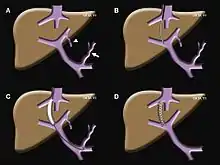

- TIPS: Placement of a Transjugular Intrahepatic Porto-systemic Shunt (TIPS) for select indications in patients with critical end-stage liver disease and portal hypertension.[10]

TIPS Procedure Schematic

TIPS Procedure Schematic - Endovenous laser treatment of varicose veins: Placement of thin laser fiber in varicose veins for non-surgical treatment of venous insufficiency.

Transjugular intrahepatic portosystemic shunt

A transjugular intrahepatic portosystemic shunt (TIPS) is a procedure an interventional radiologist performs to create a shunt (essentially, a new conduit allowing for blood flow) between the hepatic inferior vena cava and the portal vein, a vessel that returns blood from the intestines to the liver. The portal vein is the site where hypertension (high blood pressure) can produce a myriad of deleterious effects throughout the liver and small or large intestine.[19]

Primarily, a TIPS functions to alleviate two different conditions: an emergent/life-threatening GI bleed or ascites (excessive abdominal fluid) caused by too high of blood pressure in the portal vein that is otherwise uncontrolled by diet and medications.

The workup for the procedure is straightforward and the interventional radiologist performing the procedure often orders several tests to assess how well the patient will tolerate the procedure. These are often simple blood tests, and an ultrasound of the heart and liver. The procedure is often well tolerated and can result in a permanent reduction or elimination of symptoms. The procedure can take anywhere between 15 minutes to an hour and has lower risks of bleeding or infection compared to an equivalent surgical procedure.[19]

A TIPS may cause temporary confusion or worsening of liver/heart function. The degree of these two side effects largely depend on the health of the patient's heart and liver prior to the procedure and the risk-benefits of the procedure must be thoroughly discussed with their interventional radiologist before beginning. If the post-procedural consequences are more troublesome to the patient than their initial symptoms the artificial conduit created by the procedure can be reversed if the post-procedural side effects outweigh those caused by the prior conditions.[19]